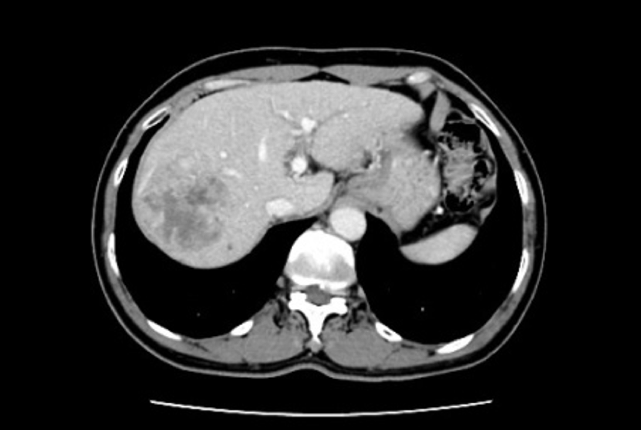

2021年11月29日上腹部MRI平扫:1)右肝癌术后及TACE术后改变。2)原肝右叶S7段结节未见确切显示,S4、S6段结节(图3)。

2021年11月29日上腹部MRI增强:1)右肝癌术后及TACE术后改变:坏死区较前稍减小;2)肝S4、S6段小结节,不典型增生结节(DN)(图3)。

2021年11月29日磁共振DWI:1)肝脏S4、S6段高信号小结节,请结合MR平扫及增强检查;2)术区液化区边缘稍高信号,请结合MR平扫及增强检查。

图3.2021年11月29日上腹部MRI平扫 增强